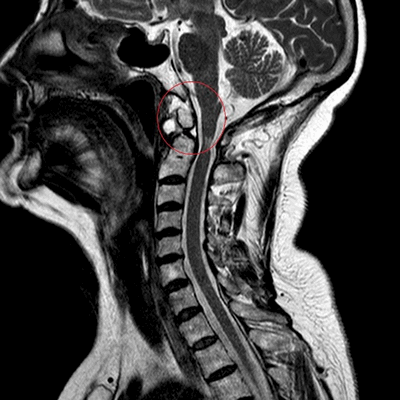

МРТ: перелом зубовидного отростка второго шейного позвонка (сагиттальная плоскость, Т2 ВИ)